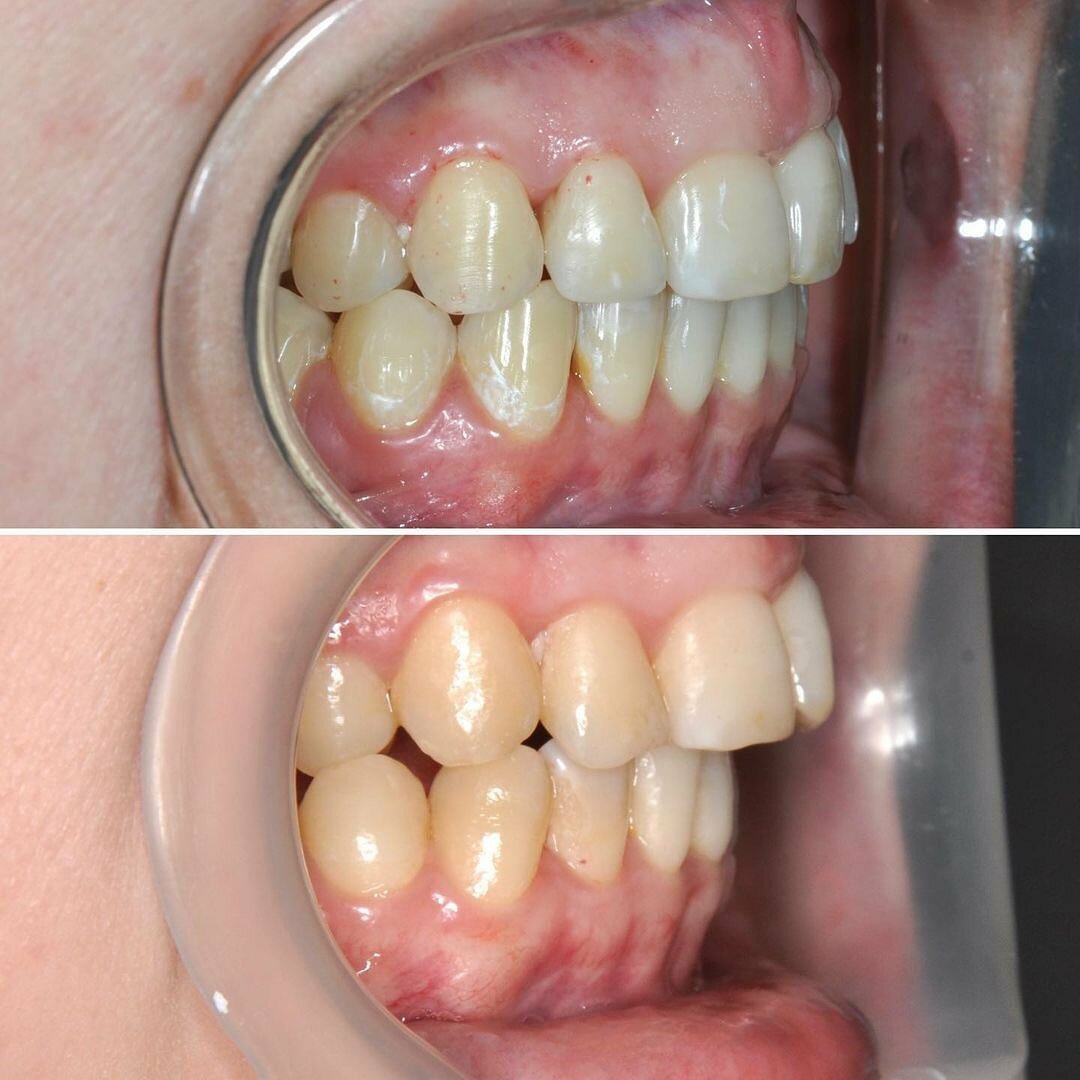

Клиника предоставляет услуги по всем основным направлениям стоматологии, включая общую стоматологию, ортодонтию, хирургическую и эстетическую стоматологию, а также детскую стоматологию. Среди дополнительных услуг: лечение кариеса, пломбирование, удаление зубов, имплантация, протезирование, отбеливание, установка виниров и брекетов, лечение десен и каналов, рентгенография, челюстно-лицевая хирургия и френулопластика.

- Отрицательные последствия лечения (выпадение зубов, испорченный прикус).

Просто отвратительно !!! После лечения зубов у Курбана Алибекова выпали все зубы !!! В место правильного прикуса я удалила все зубы! Не доктор а кошмар !!! Бегите пока не поздно !!! И пациентов лечит в одних перчатках! шок !!!!